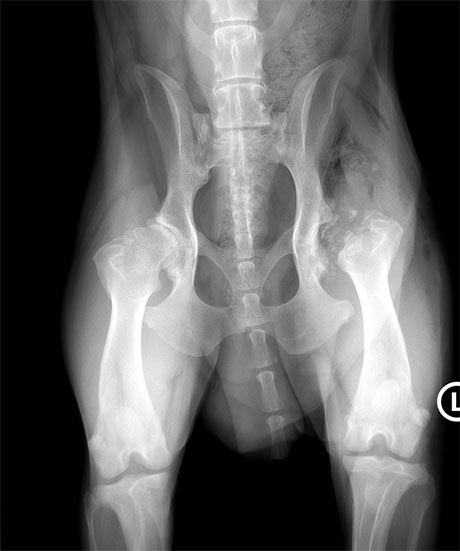

Stark ausgeprägte HD

Bei diesem 10 jährigen Labrador ist die HD stark ausgeprägt. Der linke Hüftkopf ist aus der Pfanne luxiert, starke Arthrose hat sich gebildet. Neben der Schmerzen kann das Bein nicht nach hinten gestreckt werden, da der Hüftkopf am Becken anstösst.